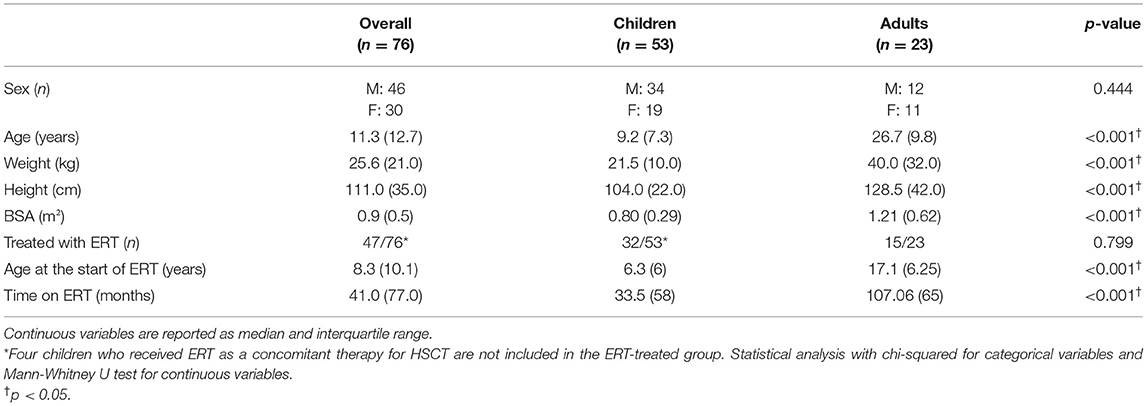

A total of 76 patients (27 MPS I, 22 MPS II, 19 MPS IVA, and 8 MPS VI), 46 males and 30 females, with a mean age of 14.2 years, being 53 children and 23 adults, were included in this study (Tables 1, 2). Most of those patients were analyzed in a previous publication, which focused on the aortic root dimension (16). All MPS II patients were males. MPS IVA patients had a lower median height, when compared to MPS II patients and were less frequently treated with ERT when compared to MPS VI patients.

Among the 76 patients included in this study, left side valvular disease was a frequent finding, with mitral and aortic thickening being reported in most patients in all four MPS types (Figure 1). Furthermore, mitral and aortic insufficiency, mostly mild, were frequently found in patients with MPS I, II, and VI, but were also observed in a significant proportion of patients with MPS IVA. To a lesser extent, tricuspid valve thickening and insufficiency were also present in patients with MPS types I, II, and VI. Heart valve involvement was both more prevalent and more severe in adult patients (Figure 2; Table 3).

Left ventricular hypertrophy parameters, including LVPWT, IVST Z scores, and RWT, were above average in a significant proportion of patients in all subgroups (Figure 3). Nevertheless, LVM Z scores were normal in the last available echocardiogram of most of the patients (Table 2). Signs of left ventricular hypertrophy were more commonly observed in children than in adults (Table 3).

When assessed the last available echocardiogram, the median left atrium diameter (LAD) and the estimated systolic pulmonary artery pressure (SPAP) were increased in patients with all types of MPS (Figures 3D,E). A total of 26 and 28% of the patients had LAD or SPAP above normal reference limits, respectively (Table 4). The median value of SPAP was significantly lower in MPS IVA than in MPS I (Figure 3D). Left ventricular ejection fraction was preserved in most patients, except for one adult patient with MPS IVA, who also had eccentric hypertrophy, severe aortic insufficiency, and moderate aortic stenosis (Figures 2A,B, 3F).

Table 4. Prevalence of echocardiographic abnormalities at the last available echocardiogram, including both ERT treated and untreated subjects.